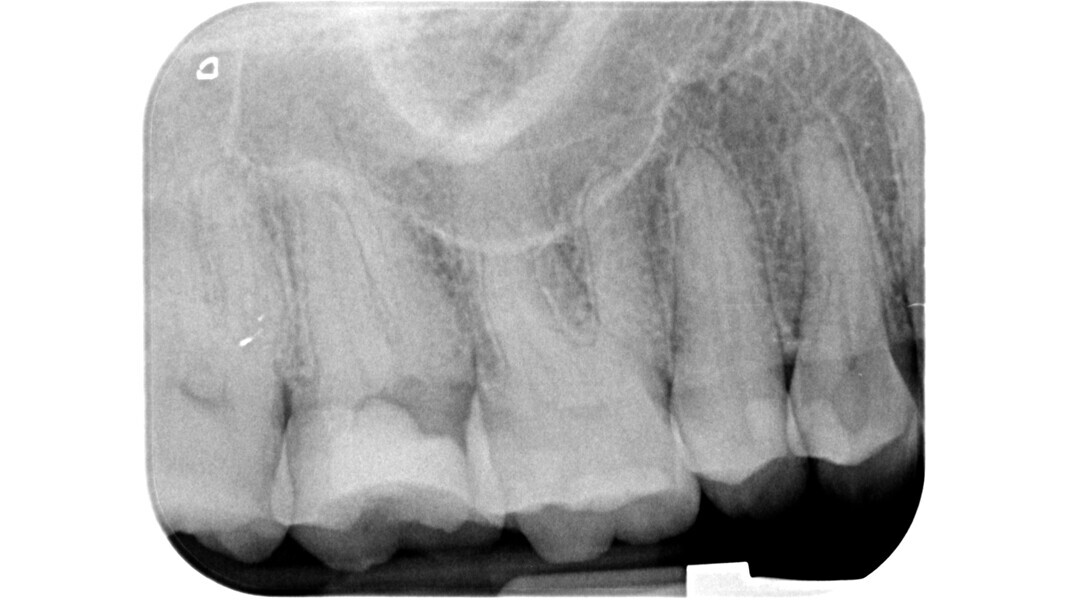

L’étape suivante est la phase de localisation et celle-ci peut s’avérer très difficile, surtout dans les dents calcifiées. Dans ce cas, le praticien doit laisser de côté les instruments rotatifs diamantés et recourir à divers dispositifs spéciaux.

La loi du changement de couleur peut être utile lors de l’approche des canaux calcifiés, puisque le praticien peut constamment distinguer les parois plus claires de la cavité pulpaire du plancher plus sombre et donc, rechercher les orifices dans cette dernière zone. Cette caractéristique est constante et sert de guide durant l’exploration des dents sclérotiques.